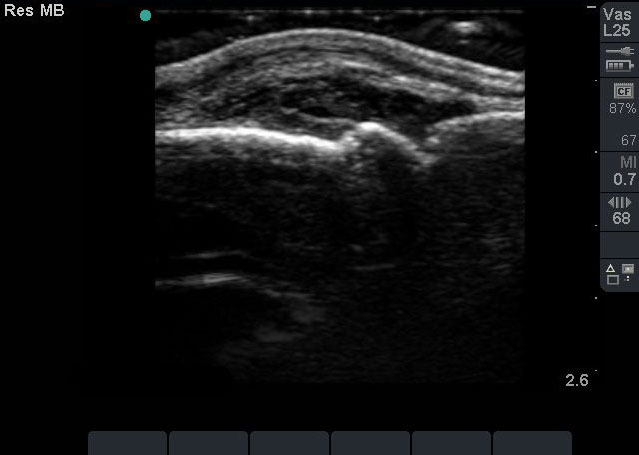

Hand Inflammatory Synovitis Image